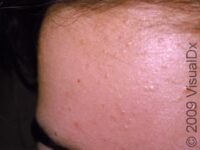

Acne (Acne Vulgaris)

Baby Acne (Neonatal Acne)